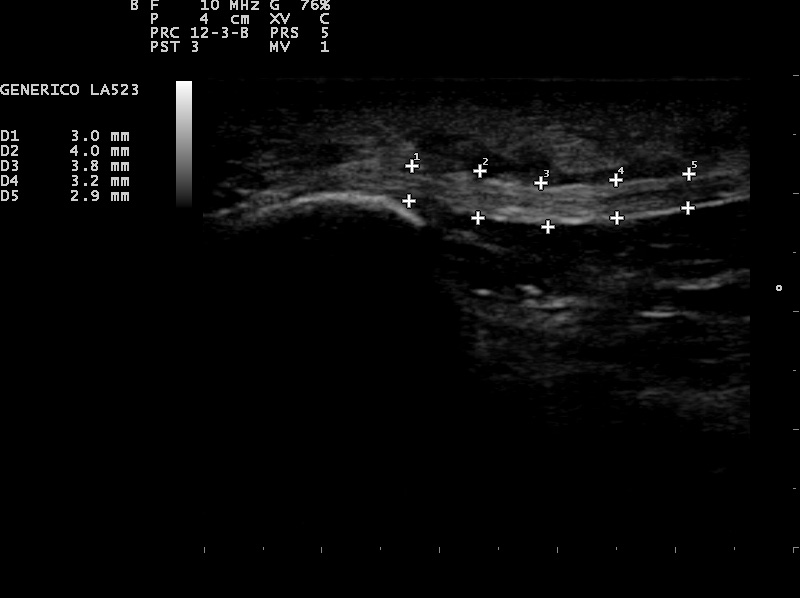

Fascia con normal

Fascia con patología